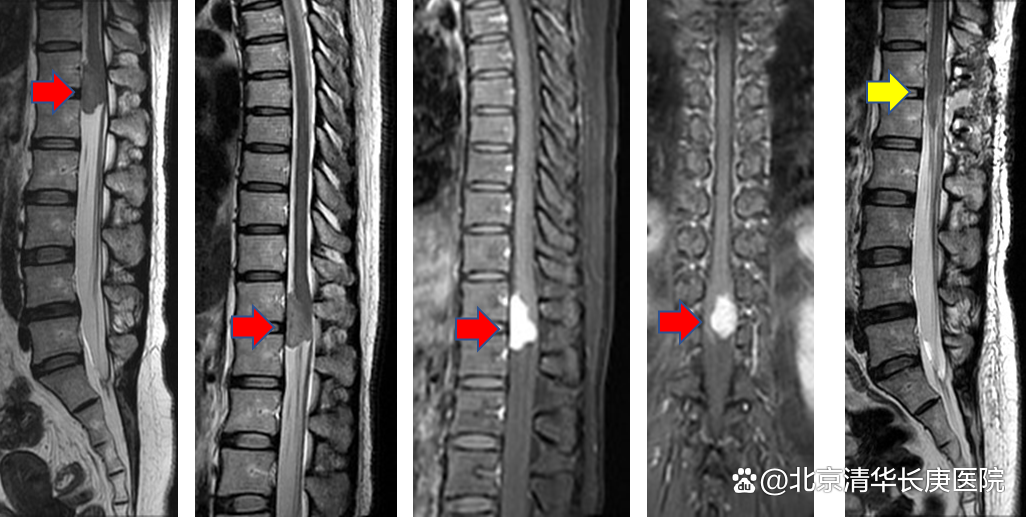

原来,在过去7个月里,杨女士一直腰背部疼痛,却始终查不出病因,直到近一个月,才通过磁共振确诊椎管里长了长约3cm的神经鞘瘤。肿瘤产生的疼痛辐射至腰背与下肢,不仅疼得整日睡不了觉,日常生活也受到了很大影响,每天服大量的止痛药也不管用。

肿瘤长约3cm

术前(红箭头)和术后(黄箭头)对比影像